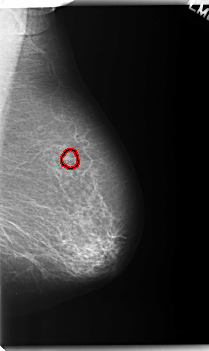

C_0231_1.RIGHT_MLO

FILE: C_0231_1.RIGHT_MLO.OVERLAY

TOTAL_ABNORMALITIES 1

ABNORMALITY 1

LESION_TYPE MASS SHAPE ROUND MARGINS ILL_DEFINED

ASSESSMENT 5

SUBTLETY 5

PATHOLOGY MALIGNANT

TOTAL_OUTLINES 1

BOUNDARY